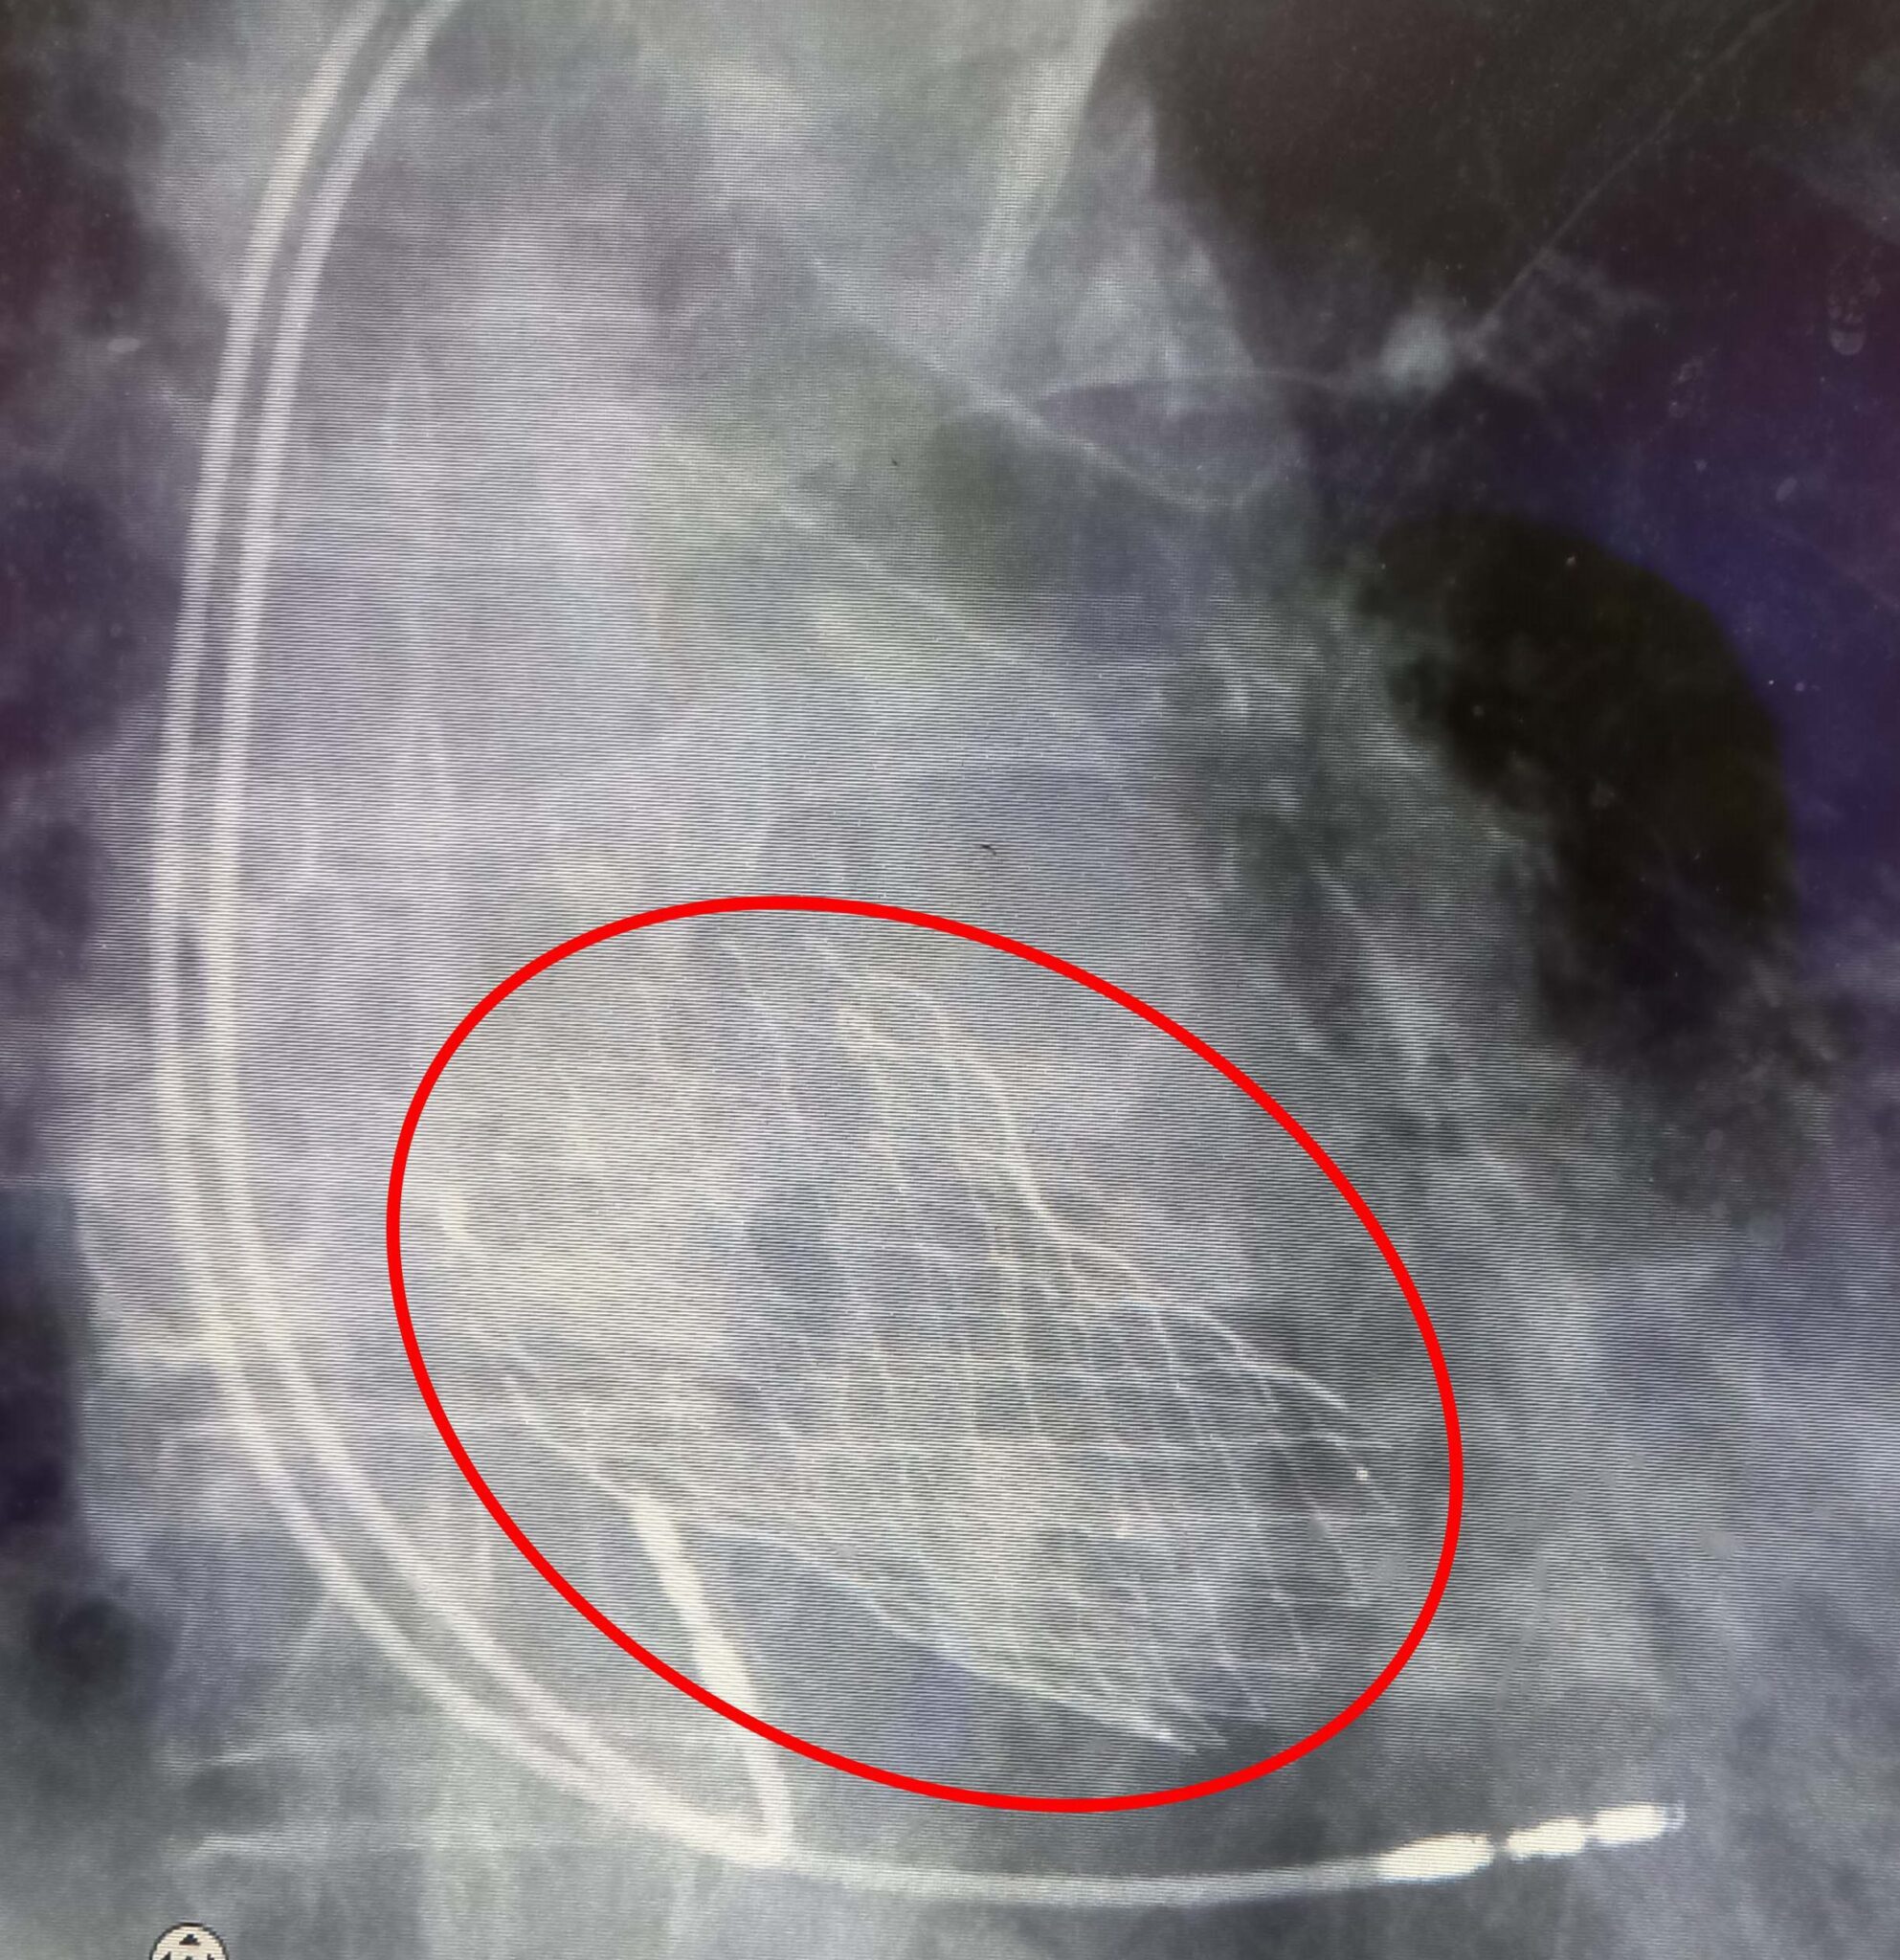

心血管外科陳胤嘉醫師指出,經導管主動脈瓣膜置換術(TAVI)通常適用於年齡在75-80歲以上的中高風險主動脈瓣膜狹窄患者;經導管主動脈瓣膜置換術相較傳統開胸手術,有傷口小、恢復快的優點,可以透過鼠蹊部股動脈或其他小切口,經導管將支架型人工瓣膜置入心臟,不僅降低手術的創傷,還讓患者能在短時間內重返日常生活。健保也可在事前申請核可的情況下給付,但是經導管主動脈瓣膜置換術,並非每位患者都適合,仍需經醫師評估。

高齡90歲的黃女士,因呼吸喘的狀況到嘉義基督教醫院求診,經心臟超音波檢查發現有嚴重主動脈狹窄合併嚴重心臟衰竭,需考慮置換人工瓣膜;考量病人年紀很大,經心臟外科陳胤嘉醫師評估後,建議進行「經導管主動脈瓣膜置換手術(TAVI)」,並由心臟血管內外科團隊陳胤嘉、張晟熙與蔡翰林醫師進行手術後順利出院。